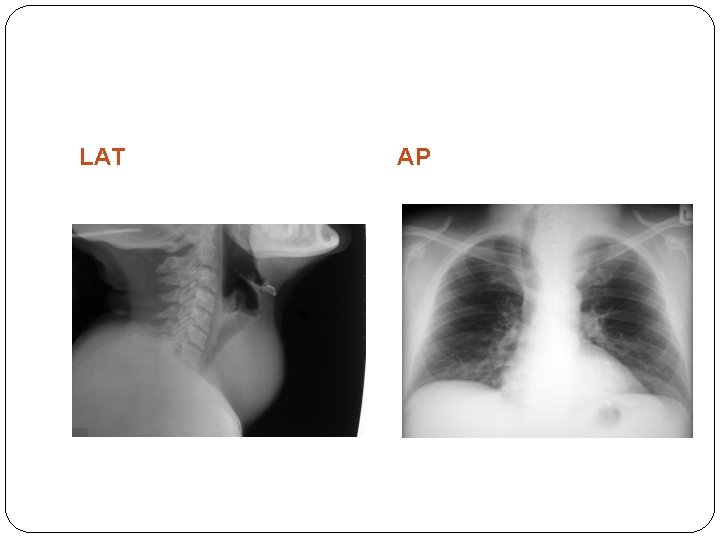

�FNAC result � Thy 1: Non-diagnostic � Thy 2: Non-neoplastic � Thy 3: Follicular � Thy 4: Suspicious for malignancy � Thy 5: Malignant � Thyroid function test: TSH is the most important � Neck X-ray: AP and Lat � Thoraxic inlet X-ray � Indirect laryngoscopy/ fibre optic laryngoscopy: : to rule out abductor cord paralysis from recurrent laryngeal nerve involvement, Laryngeal infiltration by the tumor and other Laryngeal pathology (eg hoarseness in a goitrous patient may be due to papilloma of the vocal cord)

LAT AP